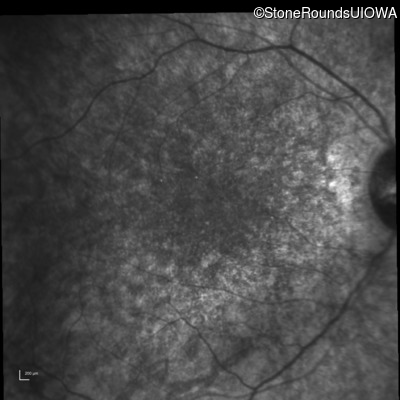

Infrared Fundus Photograph - Right - 10/140 sc

Exemplar

Infrared Fundus Photograph - Left - 10/180 sc